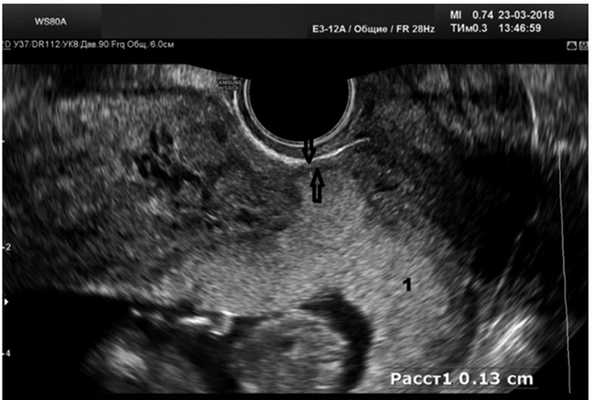

У 14 (73,7%) пациенток при типичной локализации плодного яйца в проекции рубца после кесарева сечения выявлено истончение миометрия передней стенки с остаточной толщиной миометрия менее 2 мм, деформацией передней стенки матки, «выбуханием» плодного яйца в сторону мочевого пузыря (рис. 2). В двух наблюдениях имелись признаки инвазии хориона в миометрий (рис. 3). С учетом высокого риска гестационных осложнений в виде врастания плаценты, кровотечения, разрыва матки беременным было предложено прерывание беременности с одновременной метропластикой.

Рис. 3. Беременность в рубце с признаками его несостоятельности, инвазия хориона в миометрий, высокий риск врастания плаценты.

1 — хорион; стрелками указан остаточный миометрий.